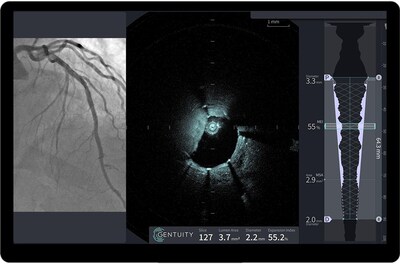

SUDBURY, Mass., Feb. 25, 2026 /PRNewswire/ -- Gentuity LLC, a Massachusetts-based medical technology company specializing in next-generation intravascular imaging devices, today announced a commercial collaboration with GE HealthCare to further improve the availability of Gentuity's HF-OCT Imaging System and Vis-Rx® PRIME Micro-Imaging Catheter. As part of the collaboration, GE HealthCare will help expand Gentuity's reach by connecting cardiac catheterization lab customers in the United States with Gentuity products. Together, Gentuity and GE HealthCare share a goal of advancing patient care by providing tools—including the High-Frequency OCT Imaging System (HF-OCT)—designed to enable more precise planning and treatment for percutaneous coronary interventions (PCIs).

Gentuity LLC is a medical technology company pioneering the next generation of intravascular imaging. Headquartered in Sudbury, Massachusetts, Gentuity is dedicated to crossing new frontiers in cardiovascular care so patients can focus on living. The company's HF-OCT Imaging System delivers the latest in intravascular OCT technology with market-leading usability, providing complete visualization to help physicians assess disease and plan treatment with confidence. Its ultra-low-profile 1.8F Vis-Rx® PRIME Micro-Imaging Catheter provides rapid 1-second, 100-mm imaging for full-vessel clarity in a single pullback, enabling real-time decision-making throughout percutaneous coronary intervention. Designed to integrate seamlessly into existing workflows, these innovations represent a new era in intravascular imaging aimed at advancing patient care.